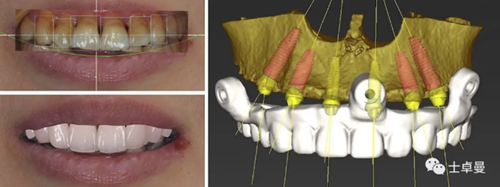

治療計劃

在前述術前評估的基礎上制定詳細的治療計劃;

通過面部和口內(nèi)相的重疊進行數(shù)字化微笑設計,以此指導虛擬排牙;

最后根據(jù)排牙信息和頜骨的骨量確定種植體的位置和型號。

計算機輔助設計最終修復體,回切后設計鈦支架形態(tài);